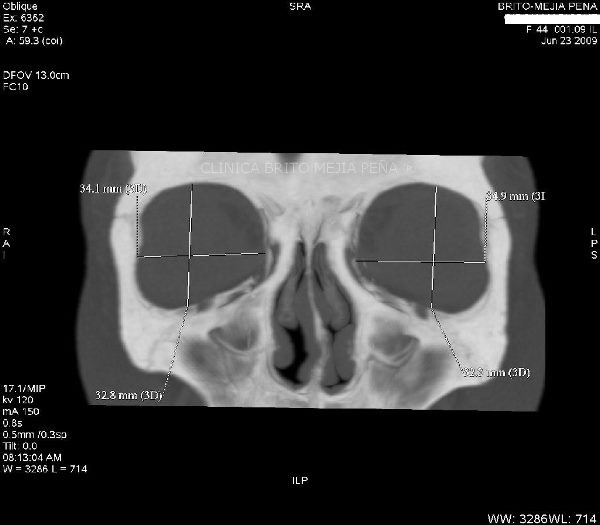

Cabeza y Cuello 2

Envíado por BMP Imágenes Diagnósticas

BMP Imágenes Diagnósticas